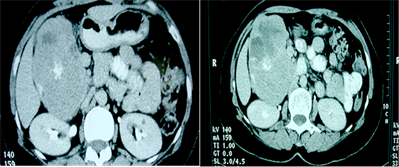

CT scan, performed with oral and intravenous contrast, upheld the findings of ultrasound revealing a large heterogeneous tissular mass in the pancreatic head, with central necrosis and calcifications (Figure 2). It showed an intense heterogeneous enhancement in the arterial phase. This mass was bounded in front by the gall bladder which is repressed, in the back by the right kidney with apparent para renal fat invasion and laterally, by digestive structures (small bowl and colon). The corporeal and caudal portions of the pancreas were normal. Moreover, intrahepatic and extrahepatic bile ducts were not dilated and no metastatic localisation was detected.

Figure 2. Abdominal computed tomography scan. (a) Computed tomography scan with oral contrast showing the calcifications within the pancreatic head mass which is repressing the gall bladder; (b) Computed tomography scan performed after oral and venous contrast in the portal phase showing an intense heterogeneous enhancement associated with necrosis within the mass; (c) Computed tomography scan performed after oral and venous contrast in the tardive phase.